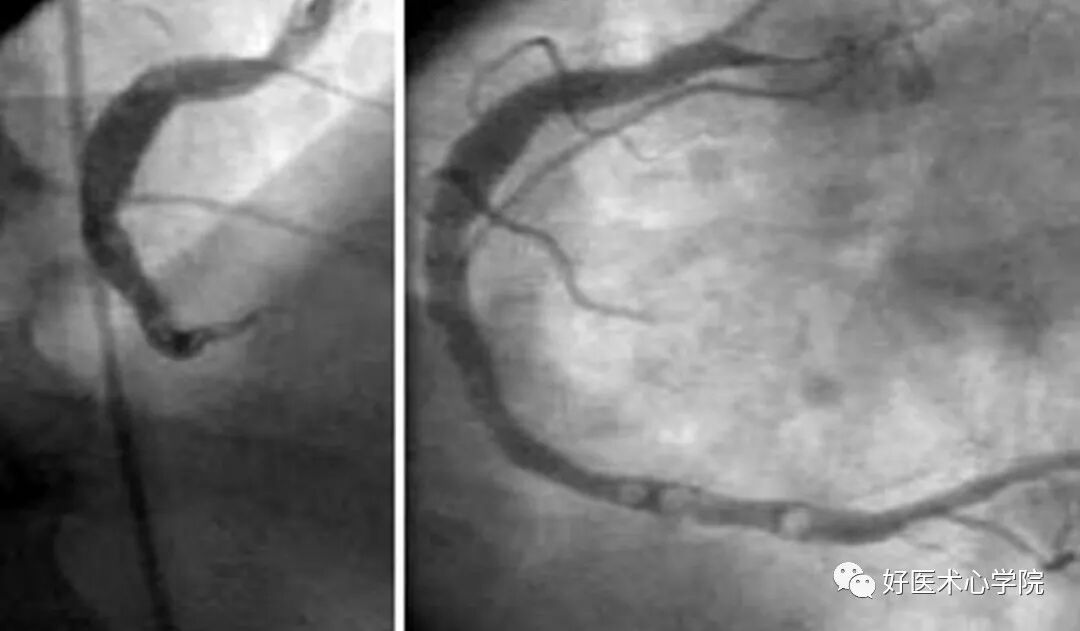

4. 血管是否有“卷须”?

前降支与对角支难以分别时,从解剖图可以看出,前降支会发出很多间隔支支配室间隔,而对角支是没有的。

造影导丝是什么珍藏 冠脉造影从流程到诊断,基础必备!_https://www.jmylbn.com_新闻资讯_第59张

左冠的右前斜位↑

左前降支水平走行于心脏上方,而左回旋支走行方向与左前降支垂直。在此位左前降支和对角支可能重叠。为确定是否为左前降支可以寻找间隔支(类似“卷须”或“梳齿”,或者找出指向心尖的血管。

造影导丝是什么珍藏 冠脉造影从流程到诊断,基础必备!_https://www.jmylbn.com_新闻资讯_第60张

左冠的左前斜位↑

左前降支向左侧走行, 对角支位于中下方, 而左回旋支位于右上方,然后向下走行。